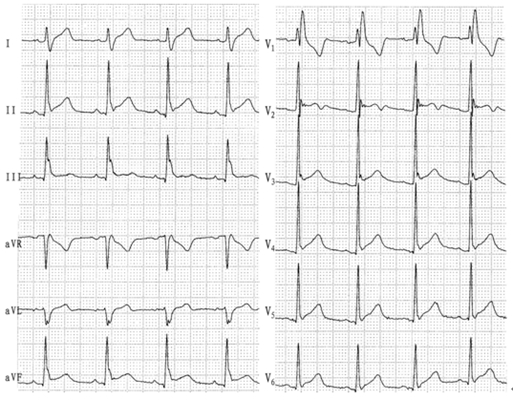

預激綜合徵心電圖 (9)

預激綜合徵心電圖 (90)

預激綜合徵心電圖 (91)

預激綜合徵心電圖 (92)

預激綜合徵心電圖 (93)

預激綜合徵心電圖 (94)

預激綜合徵心電圖 (95)

預激綜合徵心電圖 (96)

A:預激綜合徵典型的心電圖表現是竇性心搏的PR間期縮短,短於0.12s,而且導聯的QRS波群時間超過0.12s。QRS波群起始部分會有粗鈍,終末部分正常,甚至會導致ST-T波型呈現繼發性的改變,甚至於QRS波群主波方向相反。預激綜合徵是指心房……

A:預激綜合徵是很少見的心律失常,是房室傳導異常的一種類型,提早興奮心室的一部分或全部,引起心室肌提前激動,常合併室上性心動過速。心電圖可見PR間期縮短小於0.12秒;QRS時限延長0.11秒以上;QRS波群起始部粗鈍,繼發性ST-T改變。沒有……

A:預激綜合徵合併房速的時候,心電圖可以出現快速而且寬大畸形的QRS波群,有點類似於室性心動過速,典型的預激波有可能會被覆蓋。合併房速的時候會有極快速的心室率、QRS波群會寬大畸形,也有可能比較易變和複雜。患有預激綜合症合併房速,如果有明顯的心……